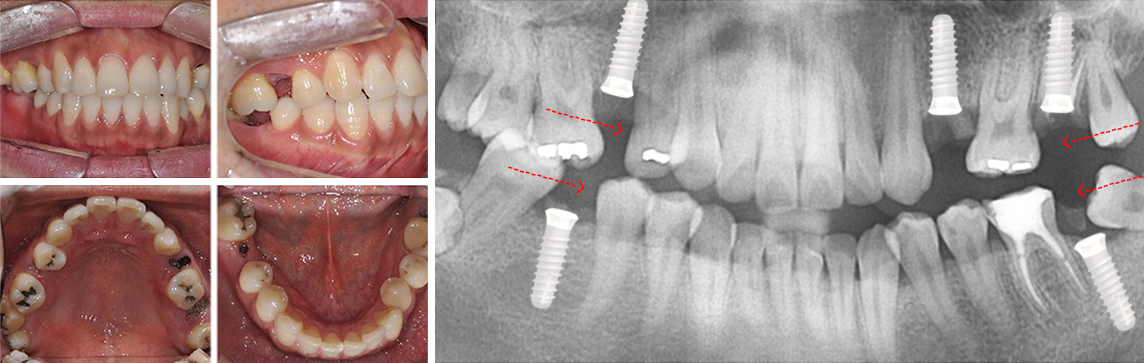

30대 남환으로 다른 치과에서 임플란트 5개 진단을 받고 내원. 교정과 협진으로 공간을 메꾸고 오른쪽 위 치아에 임플란트를

1개만 식립하여 자연치아를 최대한 활용하는 진료 계획을 세움.

다른 병원에서 임플란트 5개 진단을 받고 내원

사랑니를 빈 공간으로 이동시킴

치아가 상실된 부위 공간을 사랑니를 활용하여 모두 메워 임플란트 개수를 5개에서 1개로 감소. 또한 상실된 부위의 잇몸 뼈 높이가 높아져 예전보다

건강해 졌으며, 입술 외모가 개선되었습니다.